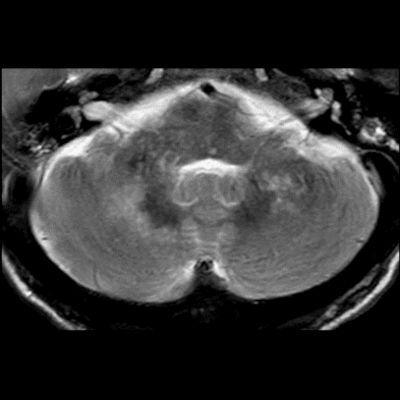

- Bilateral asimetrik subkortikal ve derin beyaz cevherde T1 ağırlıklı görüntülerde belirgin hipointens (oklar), T2A görüntülerde hiperintens (oklar), gri cevhere bakan kesimi düzgün (oklar), DAG’de hiperintens (ok) lezyonlar izlendi. Lezyonlarda T2/FLAIR uyumsuzluğu vardı (ok). Serebellar beyaz cevherde dentat nukleusu koruyan hilal işareti görüldü (ok başı). SWI sekansta sol motor kortekste hipointens kronik glioinflamatuar reaksiyon ile uyumlu sinyal değişikliği izlendi (ok başı).

- Çoğunlukla subkortikal beyaz cevherde ve U fiberlerde, asimetrik, genelde kitle etkisi yapmayan ve kontrastlanmayan demiyelinizan lezyonlar görülür. Korteks ve derin gri cevher tutulumu daha nadirdir.